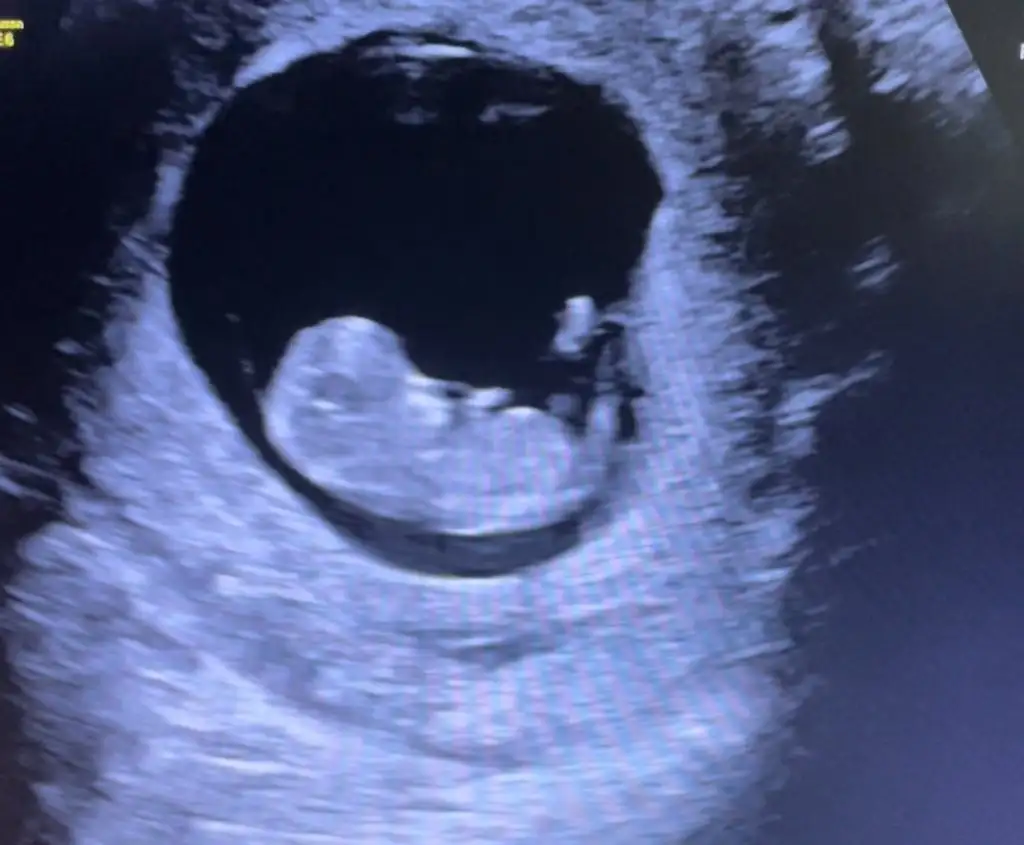

Fetal DNA iÇin kan verdim önceliğim sağlık ama doktorum cinsiyet için şu an bir şey diyemem dedi fotosunu atsam anlayacak olan var mıdır